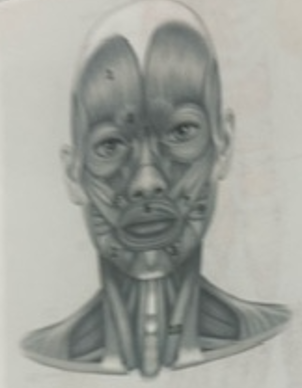

What muscle is 1?

Frontalis

What muscle is 2?

Depressor anguli oris

What muscle is 3?

Depressor labili inferioris

What muscle is 4?

Corrugator supercili

What muscle is 5?

Orbicularis oris

What muscle is 6?

Zygomaticus minor

What muscle is 7?

Zygomaticus major

What muscle is 9?

Buccinator

What muscle is 10?

Sternocleidmastoid

What muscle is 11?

Temporalis

What muscle is 12?

Masseter

What muscle is 13?

Risorius